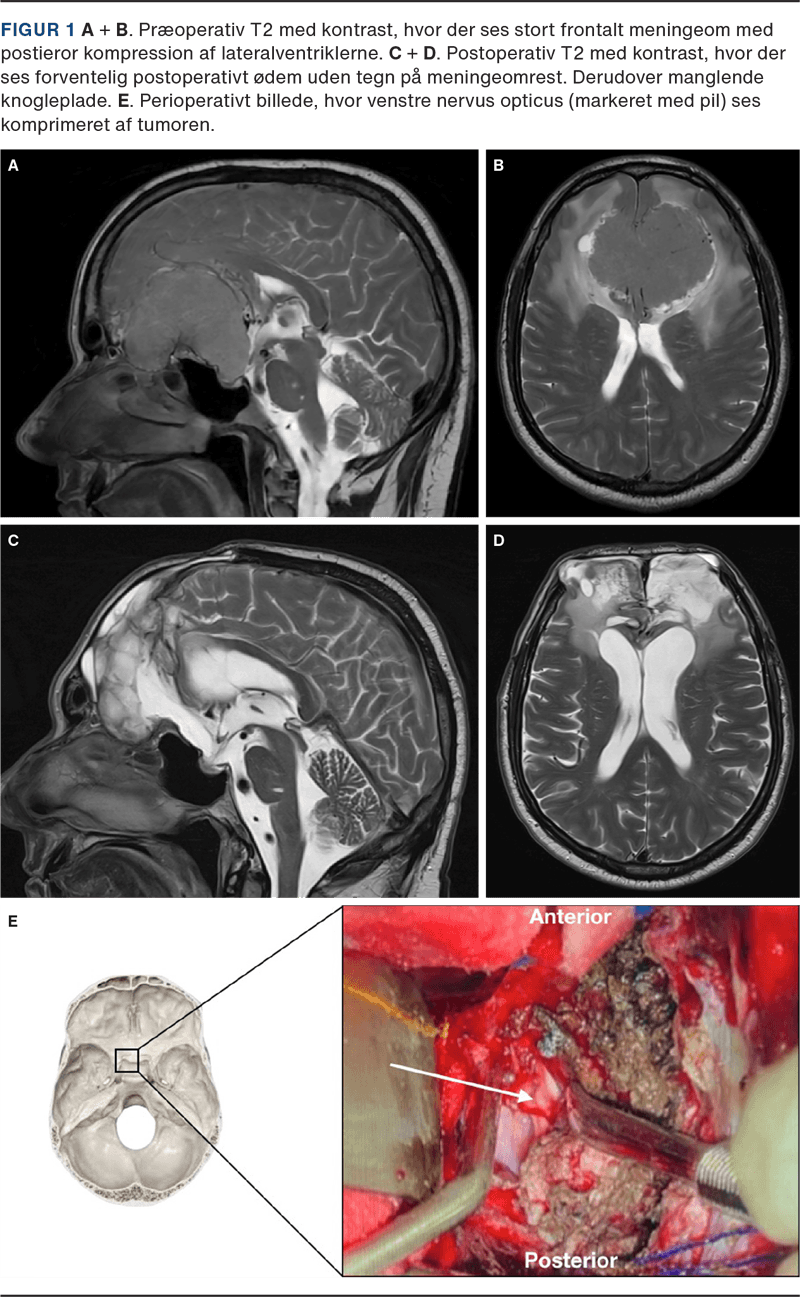

Seks år efter symptomdebut blev en MR af cerebrum udført under akut indlæggelse på grund af vedvarende hovedpine, og denne viste et kæmpe frontalt meningeom på 7 × 7 × 5 cm (Figur 1 A og B). Ved en klinisk undersøgelse fandtes ophørt lugtesans, komplet bilateralt synstab og minimal højresidig pupilreaktion. Øvrige kranienerver og kraft var bevaret. Patientens affekt var inkongruent med upassende latter.

En angiografi viste tumorvaskularisering fra begge arteriae ophthalmicae samt arteria meningea media sinister. Disse blev endovaskulært okkluderet præoperativt. Intraoperativt verificeredes bilateral kompression af nervus opticus (Figur 1 E). Meningeomet blev fuldstændigt reseceret (Simpsons resektionsgrad I), hvorfor recidivraten forventes < 20%. Knoglepladen blev ikke genanlagt på grund af postoperativt ødem, med planlagt genanlæggelse efter fire måneder. En histopatologitest viste benign tumor (WHO grad I). Patienten blev udskrevet til neurorehabilitering med fortsatte neurokognitive deficits og uden forventning om syns- eller lugtgenvinding. Ved tremåneders postoperativ MR vistes forventelige sequelae uden recidiv (Figur 1 C og D).